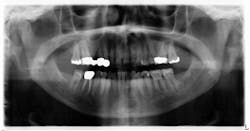

A healthy 74-year-old female presents for a comprehensive exam. A panoramic radiograph is taken. A radiopaque mass measuring approximately 0.5 x 0.5 inches is noted on the left side, just anterior to the angle of the mandible (figure 1). The area is asymptomatic upon palpation. The patient reports no knowledge of the lesion. Access to a previous pan from six years prior is acquired. The same lesion is noted on the radiograph, albeit somewhat less distinctive (figure 2).